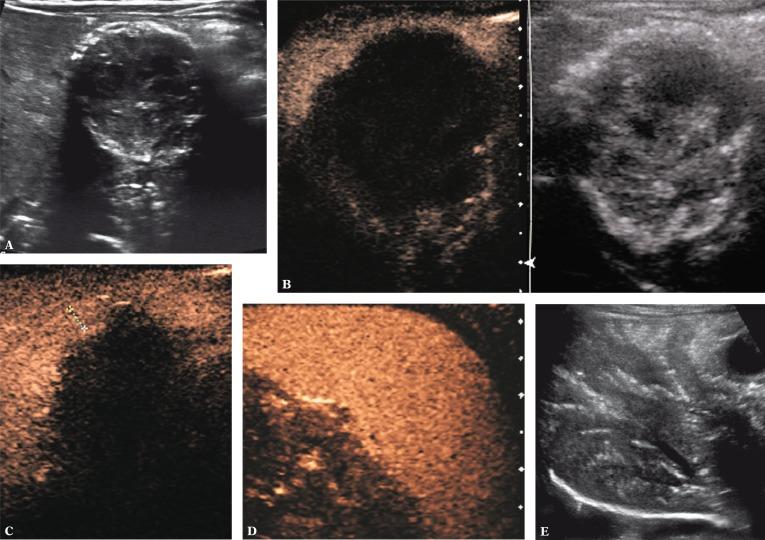

Why consider contrast-enhanced ultrasound (ce-US) in children?: Editorial comment on: M.M. Woźniak, A. Pawelec, A.P. Wieczorek, M.M. Zajączkowska, H. Borzęcka and P. Nachulewicz 2D/3D/4D contrast-enhanced voiding urosnography in the diagnosis and monitoring of treatment of vesicoureteral reflux in children - can it replace voiding cystourethrography?

Intravenous contrast-enhanced sonography in children and adolescents - a single center experience.

J Ultrason. 2013 Jun;13(53):133-44. doi: 10.15557/JoU.2013.0014. Epub 2013 Jun 30.

Safety of intravenous application of second-generation ultrasound contrast agent in children: prospective analysis.

Ultrasound elastography and contrast-enhanced ultrasound in infants, children and adolescents.

Application of a second-generation US contrast agent in infants and children--a European questionnaire-based survey.